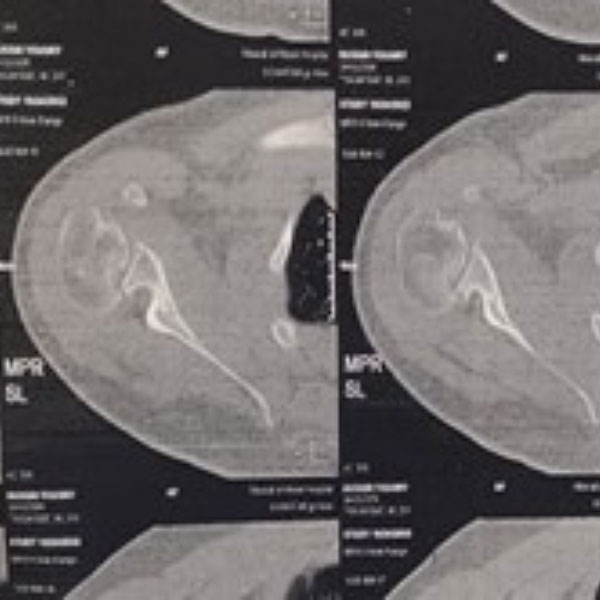

Subsequent CT and MRI scans provided clarity: the shoulder contusion had been a misdiagnosis. Instead, the patient suffered from a locked posterior shoulder dislocation. The locking occurred between an anterior defect in the humeral head, known as a reverse Hill-Sachs lesion, and the posterior glenoid rim.